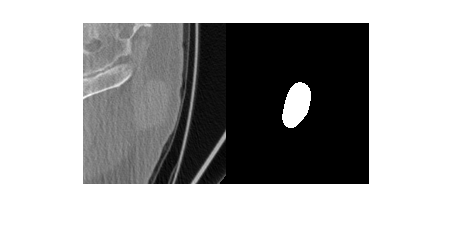

Import a computed tomography (CT) image volume and the corresponding ROI mask volume from the IBSI validation data set [1][2][3] as medicalVolume objects.

unzip("CTImageMaskNIfTI.zip") data = medicalVolume("CT_image.nii.gz"); roi = medicalVolume("CT_mask.nii.gz");

Visualize a slice of the CT image volume and the corresponding ROI.

figure

imshowpair(data.Voxels(:,:,20),roi.Voxels(:,:,20),"montage")

Create a radiomics object, using the CT image volume and ROI mask volume, with default preprocessing options.

Compute the selected features of the ROI in the CT image volume.

I = selectFeatures(R,["Sphericity3D","IntensityHistogramMode3D","Busyness25D"])

I=1×4 table

LabelID Sphericity3D IntensityHistogramMode3D Busyness25D

_______ ____________ ________________________ ___________

"1" 0.80911 10 10.072